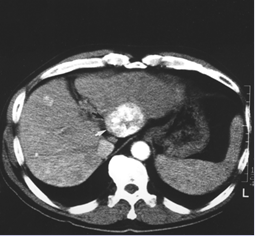

בניגוד לגידולים רבים אחרים, אבחנת סרטן כבד ראשוני אינה מחייבת ביצוע ביופסיה מהנגע הכבדי. הנחיות האיגודים המקצועיים מורות שניתן להסתפק בנגע כבדי בעל מראה אופייני בהדמיה בחולה שחמת. על הנגע להיות מודגם ב--טומוגרפיה ממוחשבת (CT, Computed Tomography) תלת פאזית או בדימות בתהודה מגנטית (MRI, Magnetic Resonance Imaging) עם גדוליניום, בעל האדרה עורקית אופיינית ושטיפה פורטלית. בדיקת PET (Positron Emission Tomography) איננה יעילה באבחון סרטן כבד ראשוני.